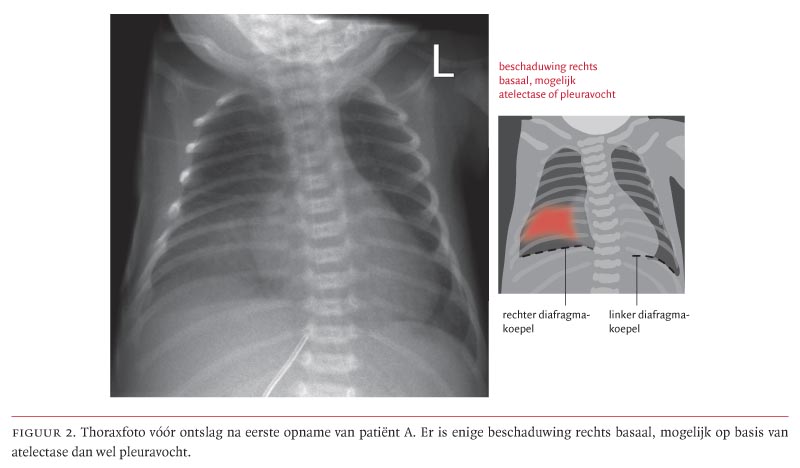

Een 1 dag oude premature zuigeling (geboren na 34 weken en 6 dagen) presenteerde zich met respiratoire insufficiëntie veroorzaakt door een pneumonie met groep B-hemolytische streptokokken (GBS). Zij knapte op na een kortdurende behandeling met beademing en antibiotica. Bij ontslag werd op de thoraxfoto nog een lichte sluiering rechts waargenomen, geduid als pleuravocht bij de pneumonie. Na 3 dagen werd patiënte opnieuw opgenomen wegens respiratoire insufficiëntie, waarvoor respiratoire ondersteuning nodig was. Bij CT-onderzoek werd een congenitale hernia diaphragmatica (CHD) rechts gezien, waarbij een groot deel van de lever en de darmen in de thorax gelegen was. Het diafragmadefect werd operatief gesloten. Na een ongecompliceerd postoperatief beloop kon patiënte in goede klinische conditie worden ontslagen. De combinatie van een vertraagde presentatie van een rechtszijdige CHD en een neonatale GBS-infectie komt zelden voor, maar is eerder beschreven. De pathogenese is onduidelijk.